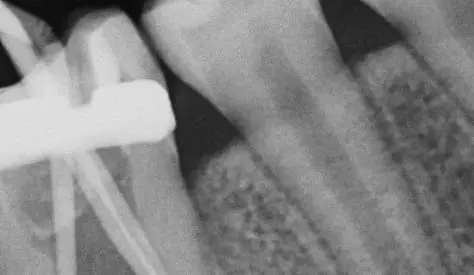

Діагностика і лікувальна тактика: коли можна не втручатись в пульпу, коли можна видаляти її частково і що робити, коли пільпа загинула. Часткова і повна пульпотомія: коли і як це робити? Що робити коли пульпа загинула повністю? Апексифікація і апексогенез, гідроксид кальцію і пробка з МТА. Останні регенераторні тенденції в ендодонтії. Реваскуляризація - що це і коли варто робити?